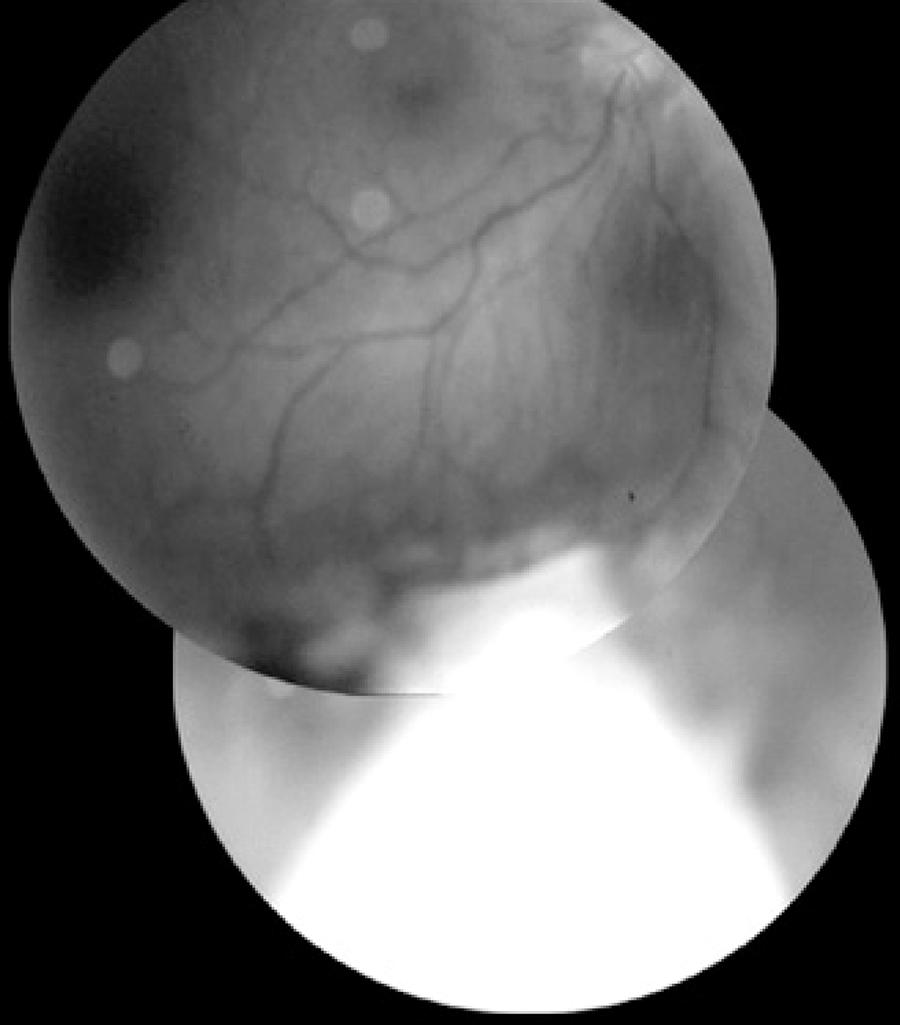

The patients (four women and one man) were aged 31-61 years. The resected tumor diameter varied between 8 mm and 15 mm, and the thickness varied between 5 mm and 11 mm. In three eyes, the tumor involved the ciliary body and choroid, and in two eyes, it involved only the choroid. The posterior limit of the latter two eyes exceeded the eye equator (Figure 2).

Figure 2 Postoperative en bloc resection of choroidal melanoma, which extended beyond the limits of the eye equator. The white area corresponds to the remaining scleral flap.